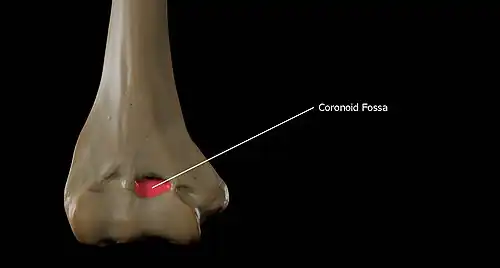

Above the front part of the trochlea is a small depression, the coronoid fossa, which receives the coronoid process of the ulna during flexion of the forearm.

The coronoid fossa is the medial hollow part on the anterior surface of the distal humerus. The coronoid fossa is smaller than the olecranon fossa and receives the coronoid process of the ulna during maximum flexion of the elbow.